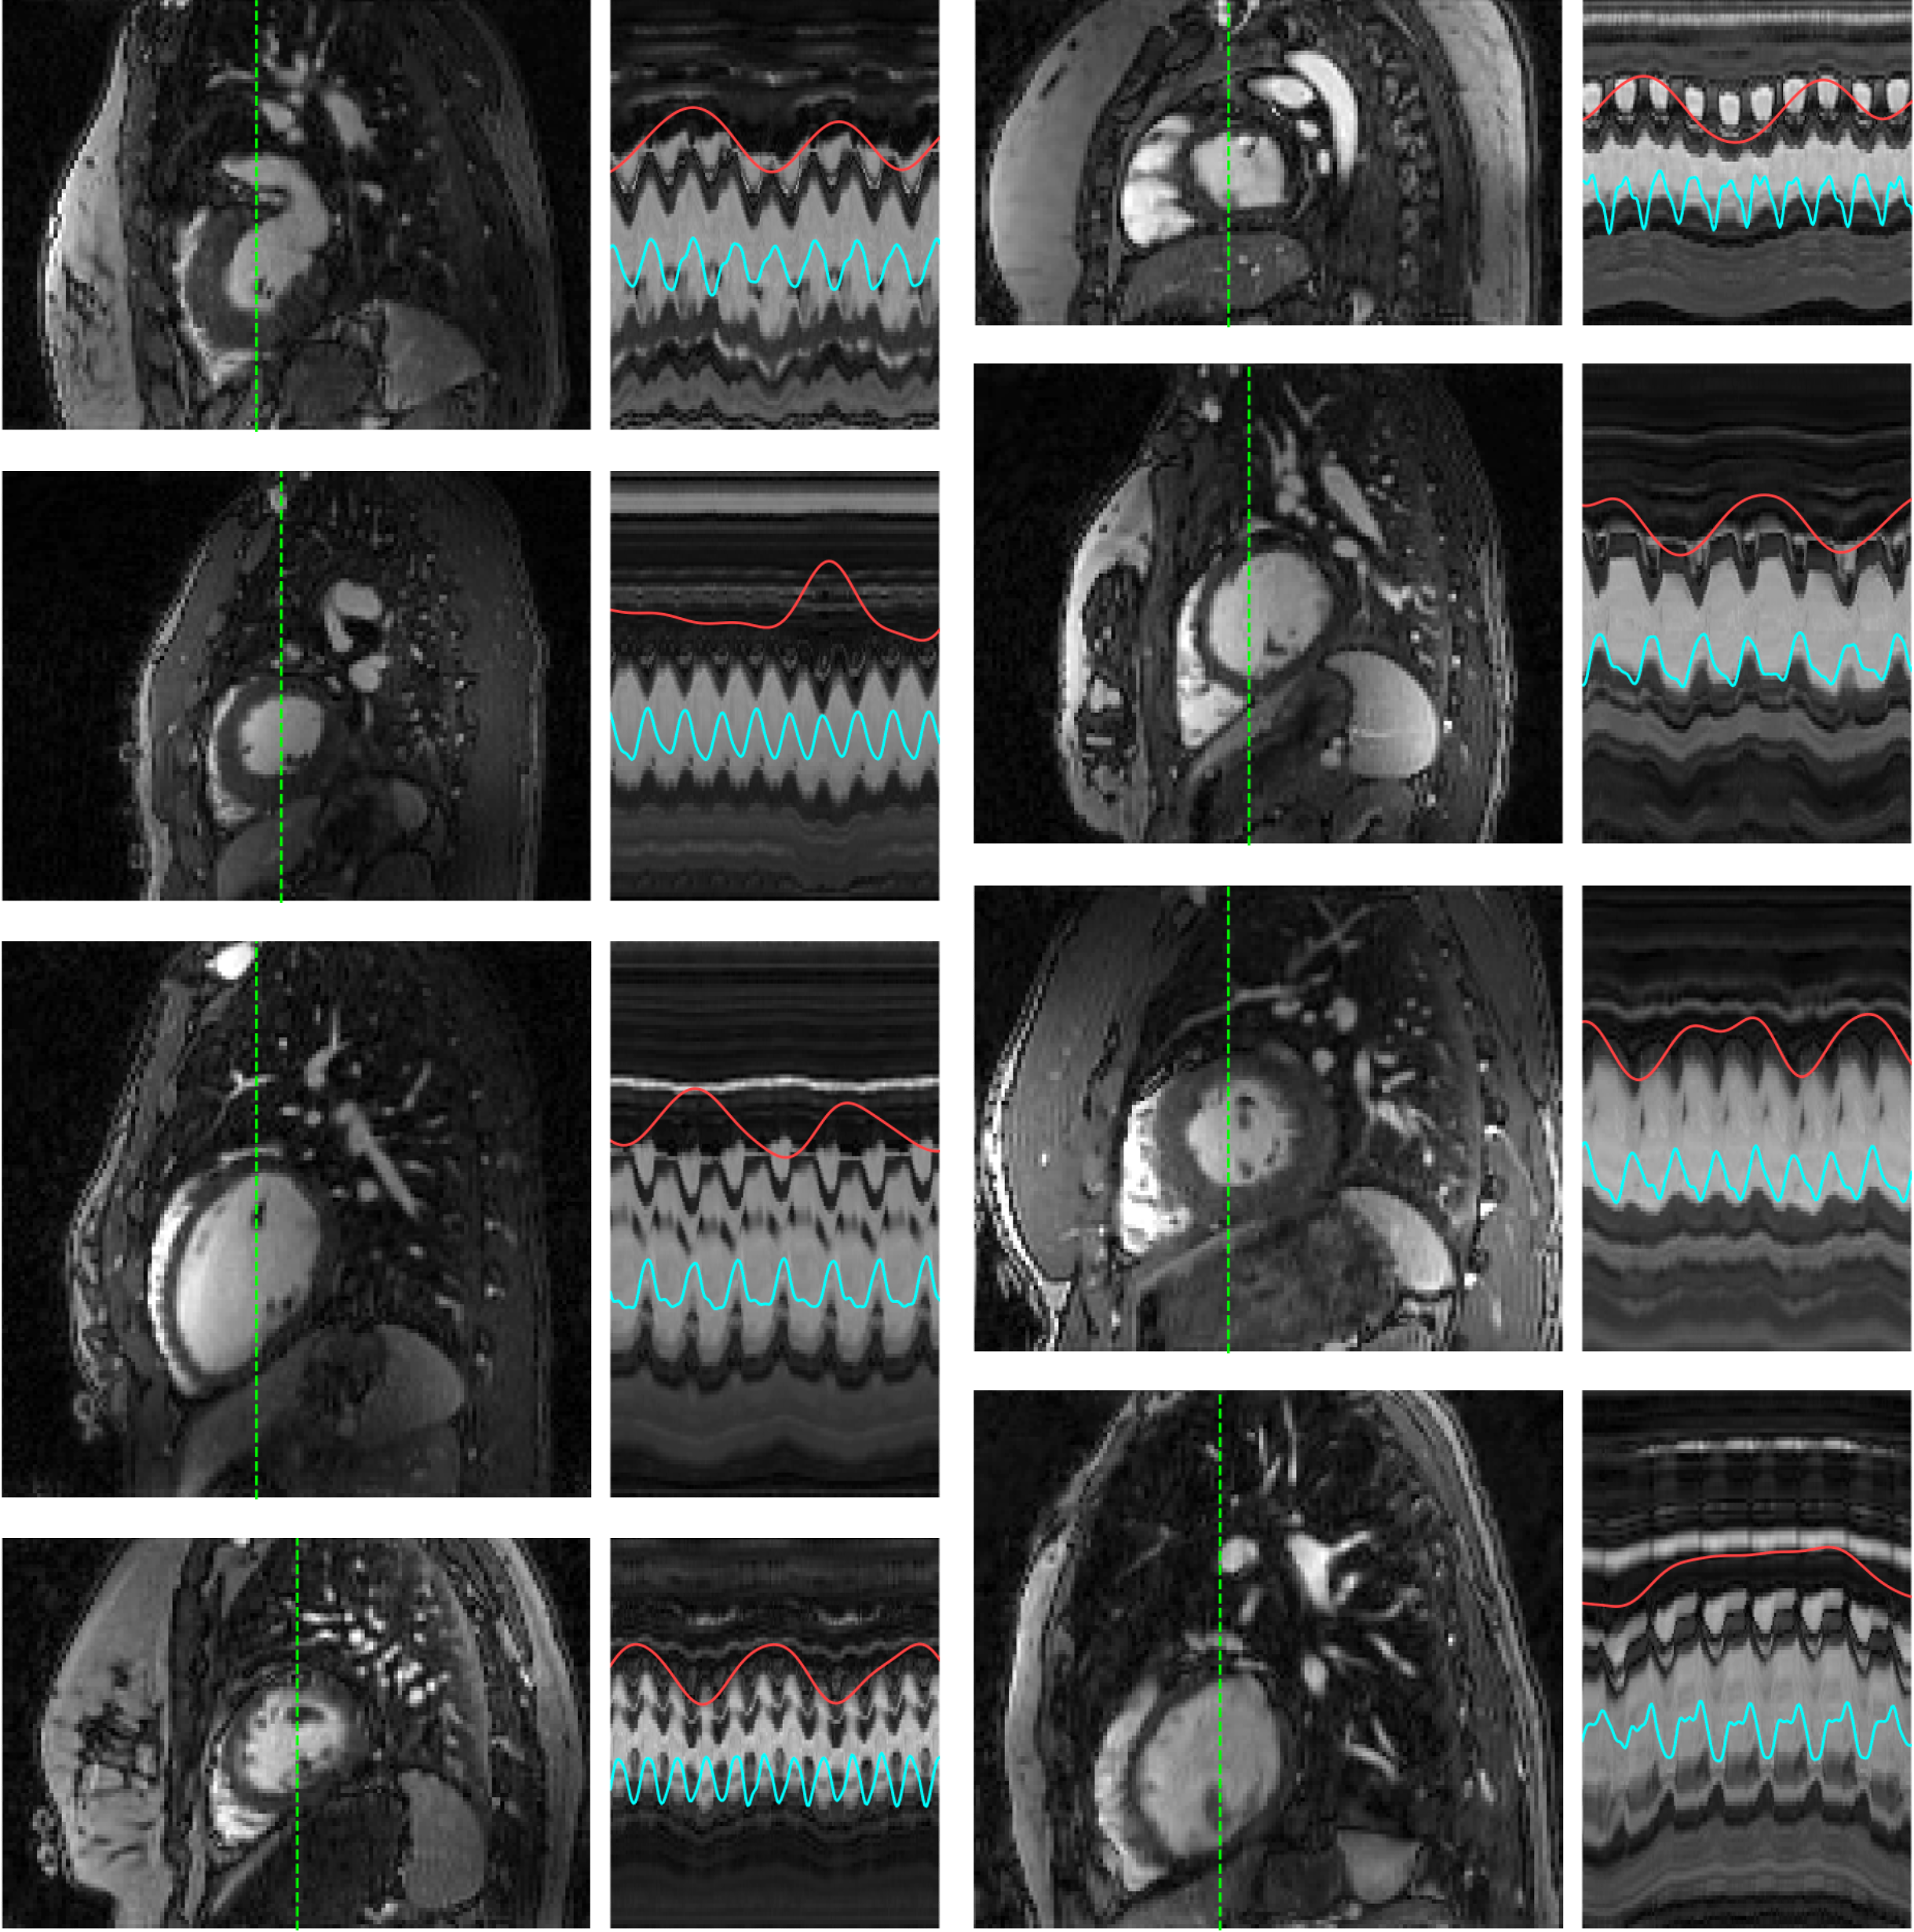

Figure 4 highlights the advantage of using a frame-specific composite image in ML-DIP. Relying on a single fixed template resulted in visible image distortions, as highlighted by the yellow arrows. Because the fixed-template approach performed poorly compared to ML-DIP, it was excluded from further comparisons. Figure 5 shows representative ML-DIP reconstructions from eight healthy volunteers scanned at rest. The corresponding x-t profiles highlight that ML-DIP preserves both cardiac and respiratory motions, closely following the self-gating signals. Figure 6 shows results from two additional volunteers scanned both at rest and during in-magnet exercise. During exercise, faster heart rates and exaggerated breathing patterns were captured without visible degradation in image quality. Figure 7 shows representative results from six of the 12 PVC patients. Despite lower blood–myocardium contrast, ML-DIP successfully captured beat-to-beat variations, including the timing and morphology of PVCs. PVC beats were easily identified on the reconstructed x–t profiles and corroborated by the self-gating signals.

Figure 5: Representative ML-DIP images in sagittal orientation from eight subjects imaged at rest. Time profiles along the dashed green lines are shown to the right of the images. Each x–t profile spans 200 frames (6.6 s). The red and cyan curves represent self-gating-based respiratory and cardiac signals, respectively.